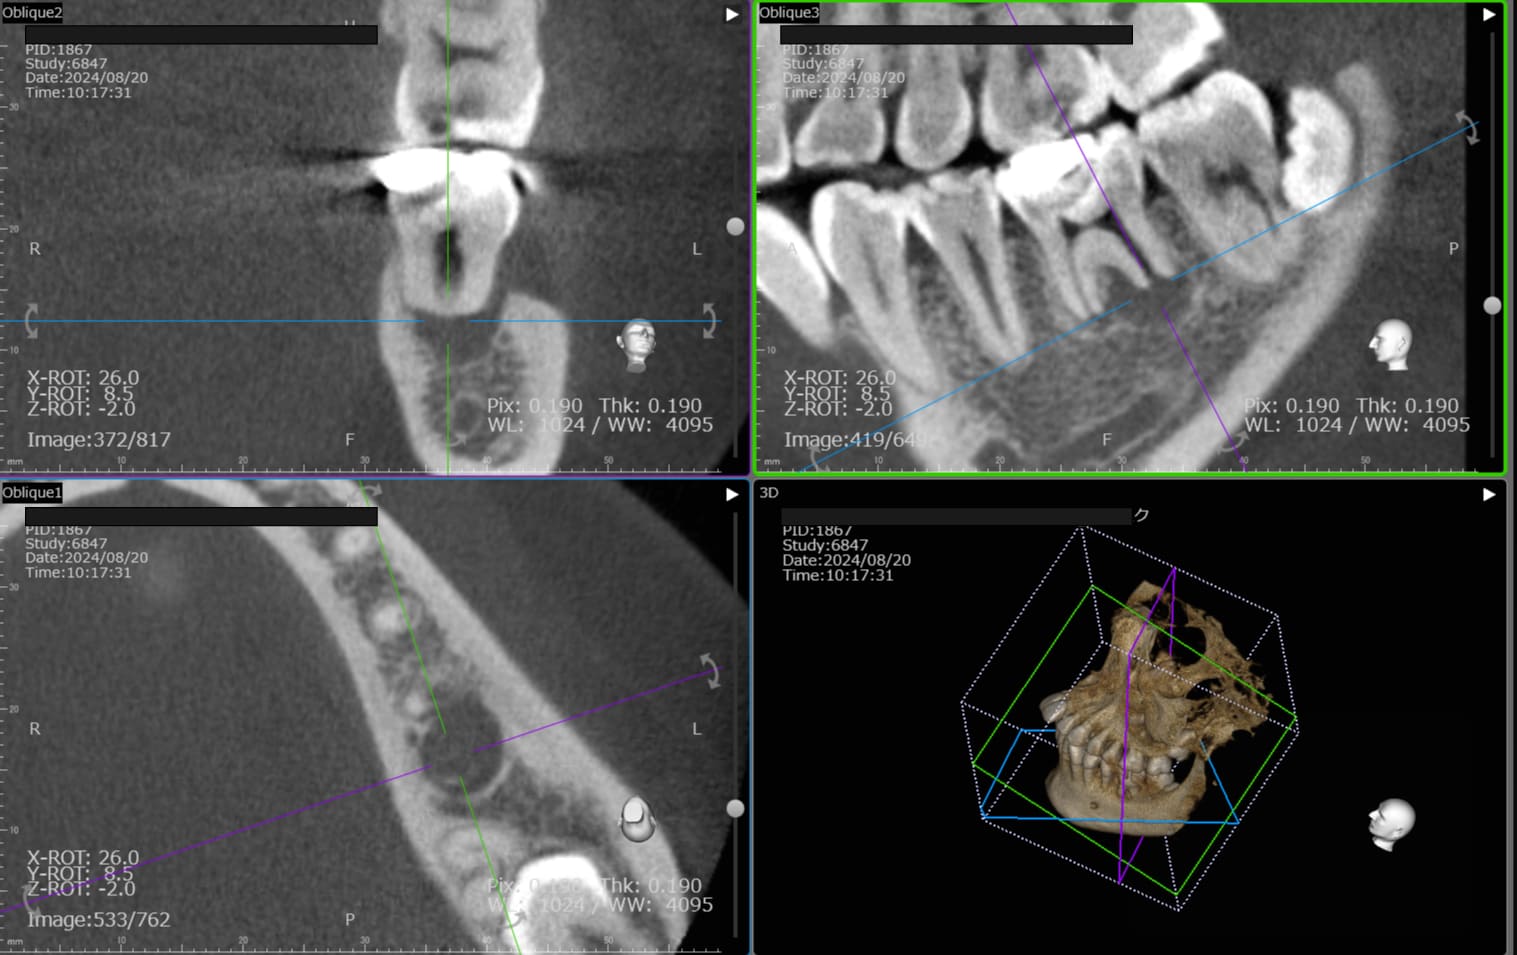

| 歯科用CTによる三次元診断 | 拡大ルーペの使用 |

| 一般的なレントゲン(二次元)では見えない、歯根の複雑な構造や病巣の位置を立体的に正確に把握し、治療の見落としを防ぎます。 | 肉眼では困難な根管内の細部を約8倍に拡大して確認し、処置の精度を高めます。 |

| 歯科用CTによる三次元診断 |

| 一般的なレントゲン(二次元)では見えない、歯根の複雑な構造や病巣の位置を立体的に正確に把握し、治療の見落としを防ぎます。 |